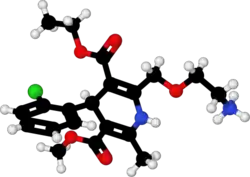

| Formula | C20H25ClN2O5 |

| Molar mass | 408.88 g·mol−1 |

| 3D model (JSmol) | |

| Chirality | Racemic mixture |